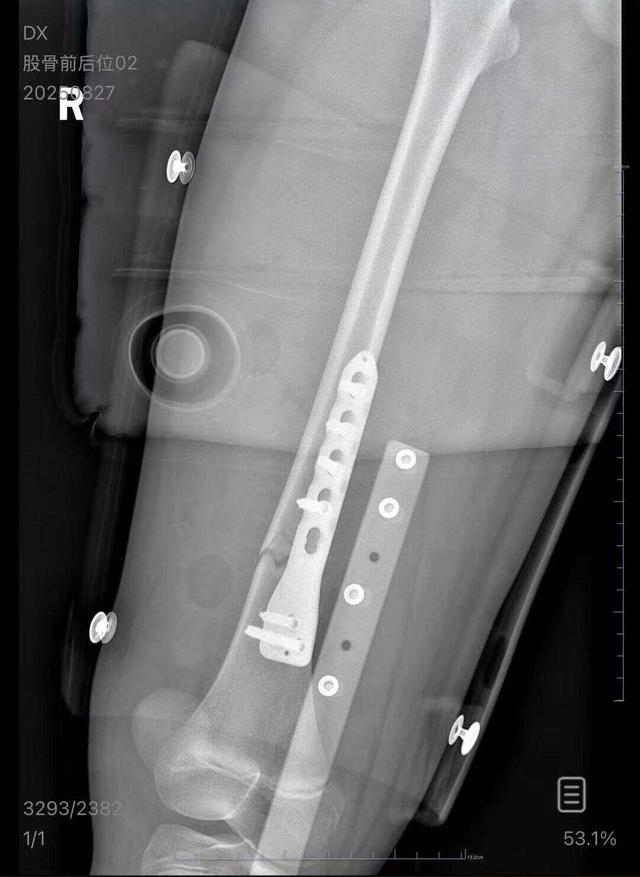

朱女士向记者出示的医院病历显示,8月24日凌晨,朱女士的女儿到医院就诊。医院诊断朱女士的女儿右股骨骨折,需要住院进一步治疗。

列车上铺乘客跌落砸断下铺10岁孩子腿骨

近日,朱女士在“腾讯热问”上发帖讲述,她今年8月带着孩子乘坐火车时,一名男乘客从上铺摔落,砸到了睡在下铺的孩子的大腿,导致孩子股骨骨折。这名男乘客虽然陪同她们去了医院,但孩子做完手术后,对方表示手头没钱,要回去筹钱。9月上旬,男子最后接了一次朱女士的电话,随后朱女士再也无法联系到对方。